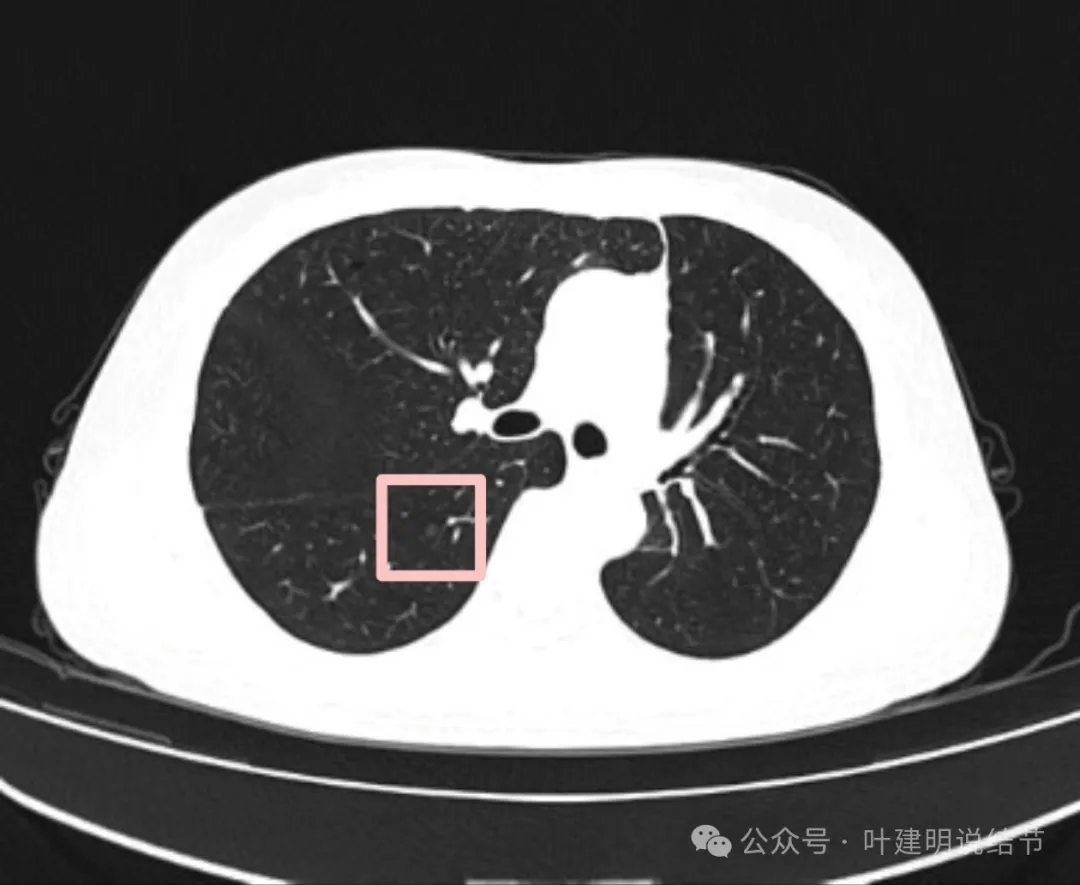

影像展示与分析:

左下叶主病灶实性,收缩力较弱,胸膜略有牵拉,表面似乎较为光滑,毛刺不明显,血管征不明显,整体密度显得较高。

纵隔窗可见。

局部放大了看,边缘略毛糙;胸膜略牵拉;灶内有小区域密度偏低的空泡或偏低密度区;表面似有较为勉强的分叶征的样子。但整体说不上明显收缩力,磨玻璃成分也不大明显。

我看有所异常的就是这几处(次要病灶未展示)。桔色圈起来的过小过淡的磨玻璃结节,考虑肺泡上皮增生可能性大,感觉没到不典型增生,先年度随访;黄色圈起来的微小实性,考虑良性的;蓝色的这处密度高,似乎良性的可能性大,但一是随访有增大,二是有胸膜牵拉,三是位置好,而若真恶性,实性风险大。我个人倾向4-6个月后左下叶靶扫描下,如果有恶性可能,则还是手术切了化验比较放心。意见供参考!